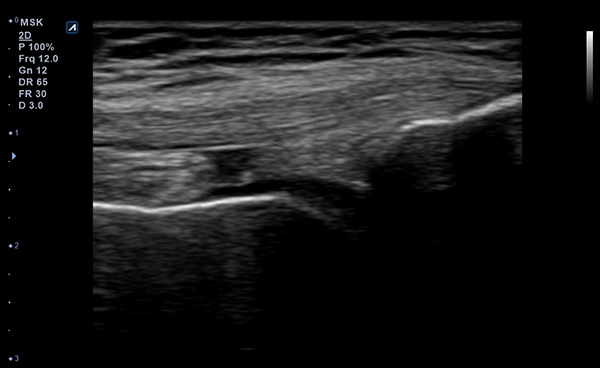

- Frequency3-12 MHz

- Dimension (height/width/depth)25.2 / 62.5/ 150mm

- Weight 175g

- Field of view 38.4mm

- Max depth10 cm

- Imaging modesB-mode, CF, M, PW, PD

- DisplayMicrosoft Surface

- Battery300 min